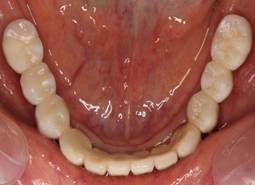

下顎

下顎。12か月に一度メインテナンスをしています。

インプラント装着後6年。順調に経過しています。12か月毎のメインテナンスをしています。